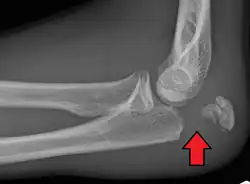

Olecranon fracture

To assess an olecranon fracture, a careful skin exam is performed to ensure there is no open fracture. Then a complete neurological exam of the upper limb should be documented.[5][2] Frontal and lateral X-ray views of the elbow are typically done to investigate the possibility of an olecranon fracture.[1] A true lateral x-ray is essential to determine the fracture pattern, degree of displacement, comminution, and the degree of articular involvement.